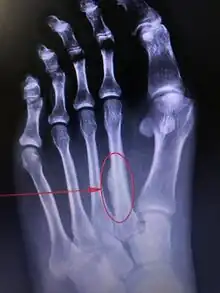

![]() | |

| Stress fracture of the second metatarsal bone | |